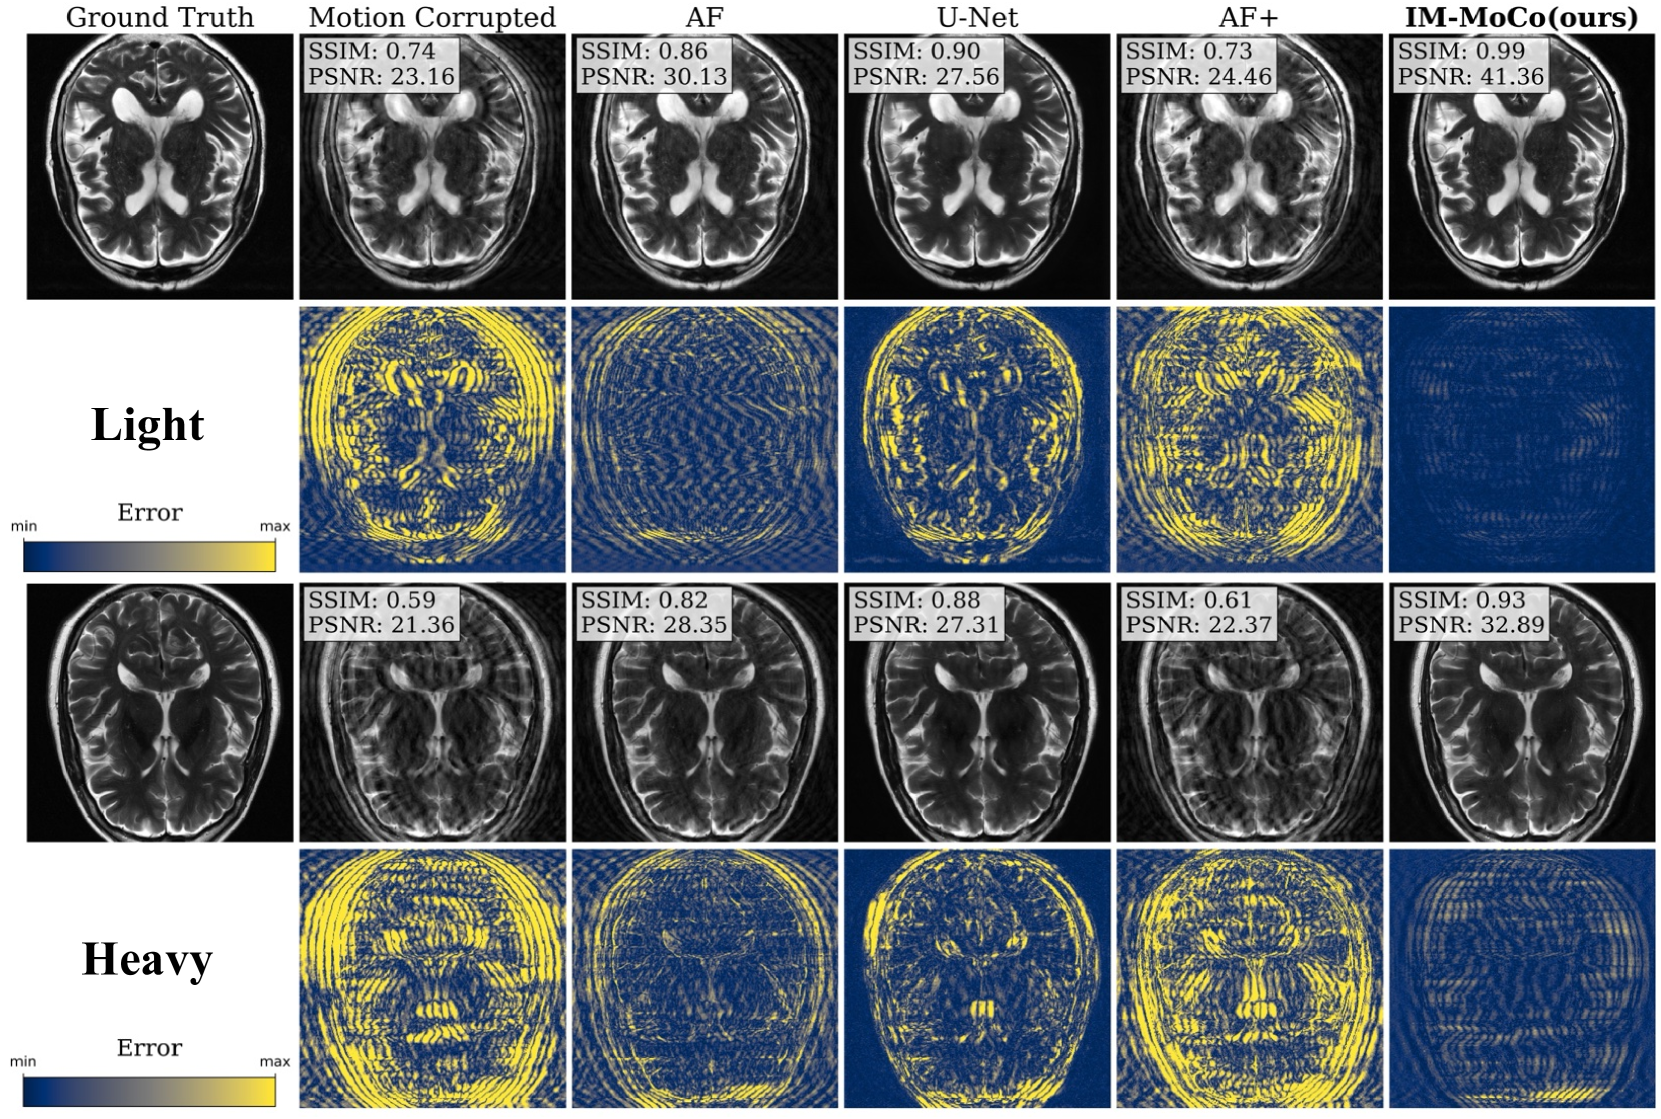

Experiment I: Motion Correction in Simulated Data. Table 1 shows quantitative results from the motion correction experiment. For light and heavy motion, corrupted images yield SSIM values of 87%percent8787\%87 % and 74%percent7474\%74 %, PSNR values of 28db28𝑑𝑏28\>db28 italic_d italic_b and 24db24𝑑𝑏24\>db24 italic_d italic_b, and HaarPSI values of 70%percent7070\%70 % and 56%percent5656\%56 %, respectively. AF and U-Net improve SSIM by 7%percent77\%7 % and 10%percent1010\%10 %, PSNR by 5db5𝑑𝑏5\>db5 italic_d italic_b and 3db3𝑑𝑏3\>db3 italic_d italic_b, and HaarPSI by 18%percent1818\%18 % and 16%percent1616\%16 %, respectively. However, AF+ worsens results by ca. 2%percent22\%2 % across all metrics. Compared to the best baseline, AF, our method improves SSIM/HaarPSI by >4%absentpercent4>4\%> 4 % for SSIM, >9%absentpercent9>9\%> 9 % for HaarPSI, and >10dbabsent10𝑑𝑏>10\>db> 10 italic_d italic_b for PSNR. A qualitative comparison is shown in Fig. 2.

Refer to caption

Figure 2: The visualization shows the median results of motion-corrected images of our IM-MoCo pipeline besides motion-corrupted, ground truth, and comparison methods. The first and third rows show the light and heavy correction results, respectively. The second and fourth rows show the residual error images.

Experiment I demonstrated that our method effectively enhanced the quality of motion-corrupted images, surpassing comparison methods, which is mainly contributed by the implicit image priors and DC with the acquired k𝑘kitalic_k-space in the forward motion model. Notably, our approach exhibited robustness in addressing heavier motion scenarios as evidenced in Fig. 2 and Table 1. However, the efficacy of our method hinges on the accurate detection of the k𝑘kitalic_klD-Net, which is contingent upon the acquisition sequence and motion simulation pattern. In Experiment II, we showcased the performance enhancement of a classification task compared to both corrupted and U-Net-corrected images as indicated in Table 2. This improvement in classification accuracy can be attributed to the prevention of overfitting on "healthy" features in instance-optimization methods in contrast to population training ones like the U-Net. Although our work primarily revolved around 2D rigid motion, we are confident in the method’s potential for extension to more complex motion and multi-coil data. This can be achieved by incorporating coil sensitivity map estimation following the third step of the pipeline. Future investigations will explore the utilization of different sampling patterns, such as radial sampling, and the adaptation of the motion detection network to these patterns or pattern-independent methods. While real motion cases were not tested in this study, we are optimistic regarding the adaptability of our method through adjustments to the motion detection network.